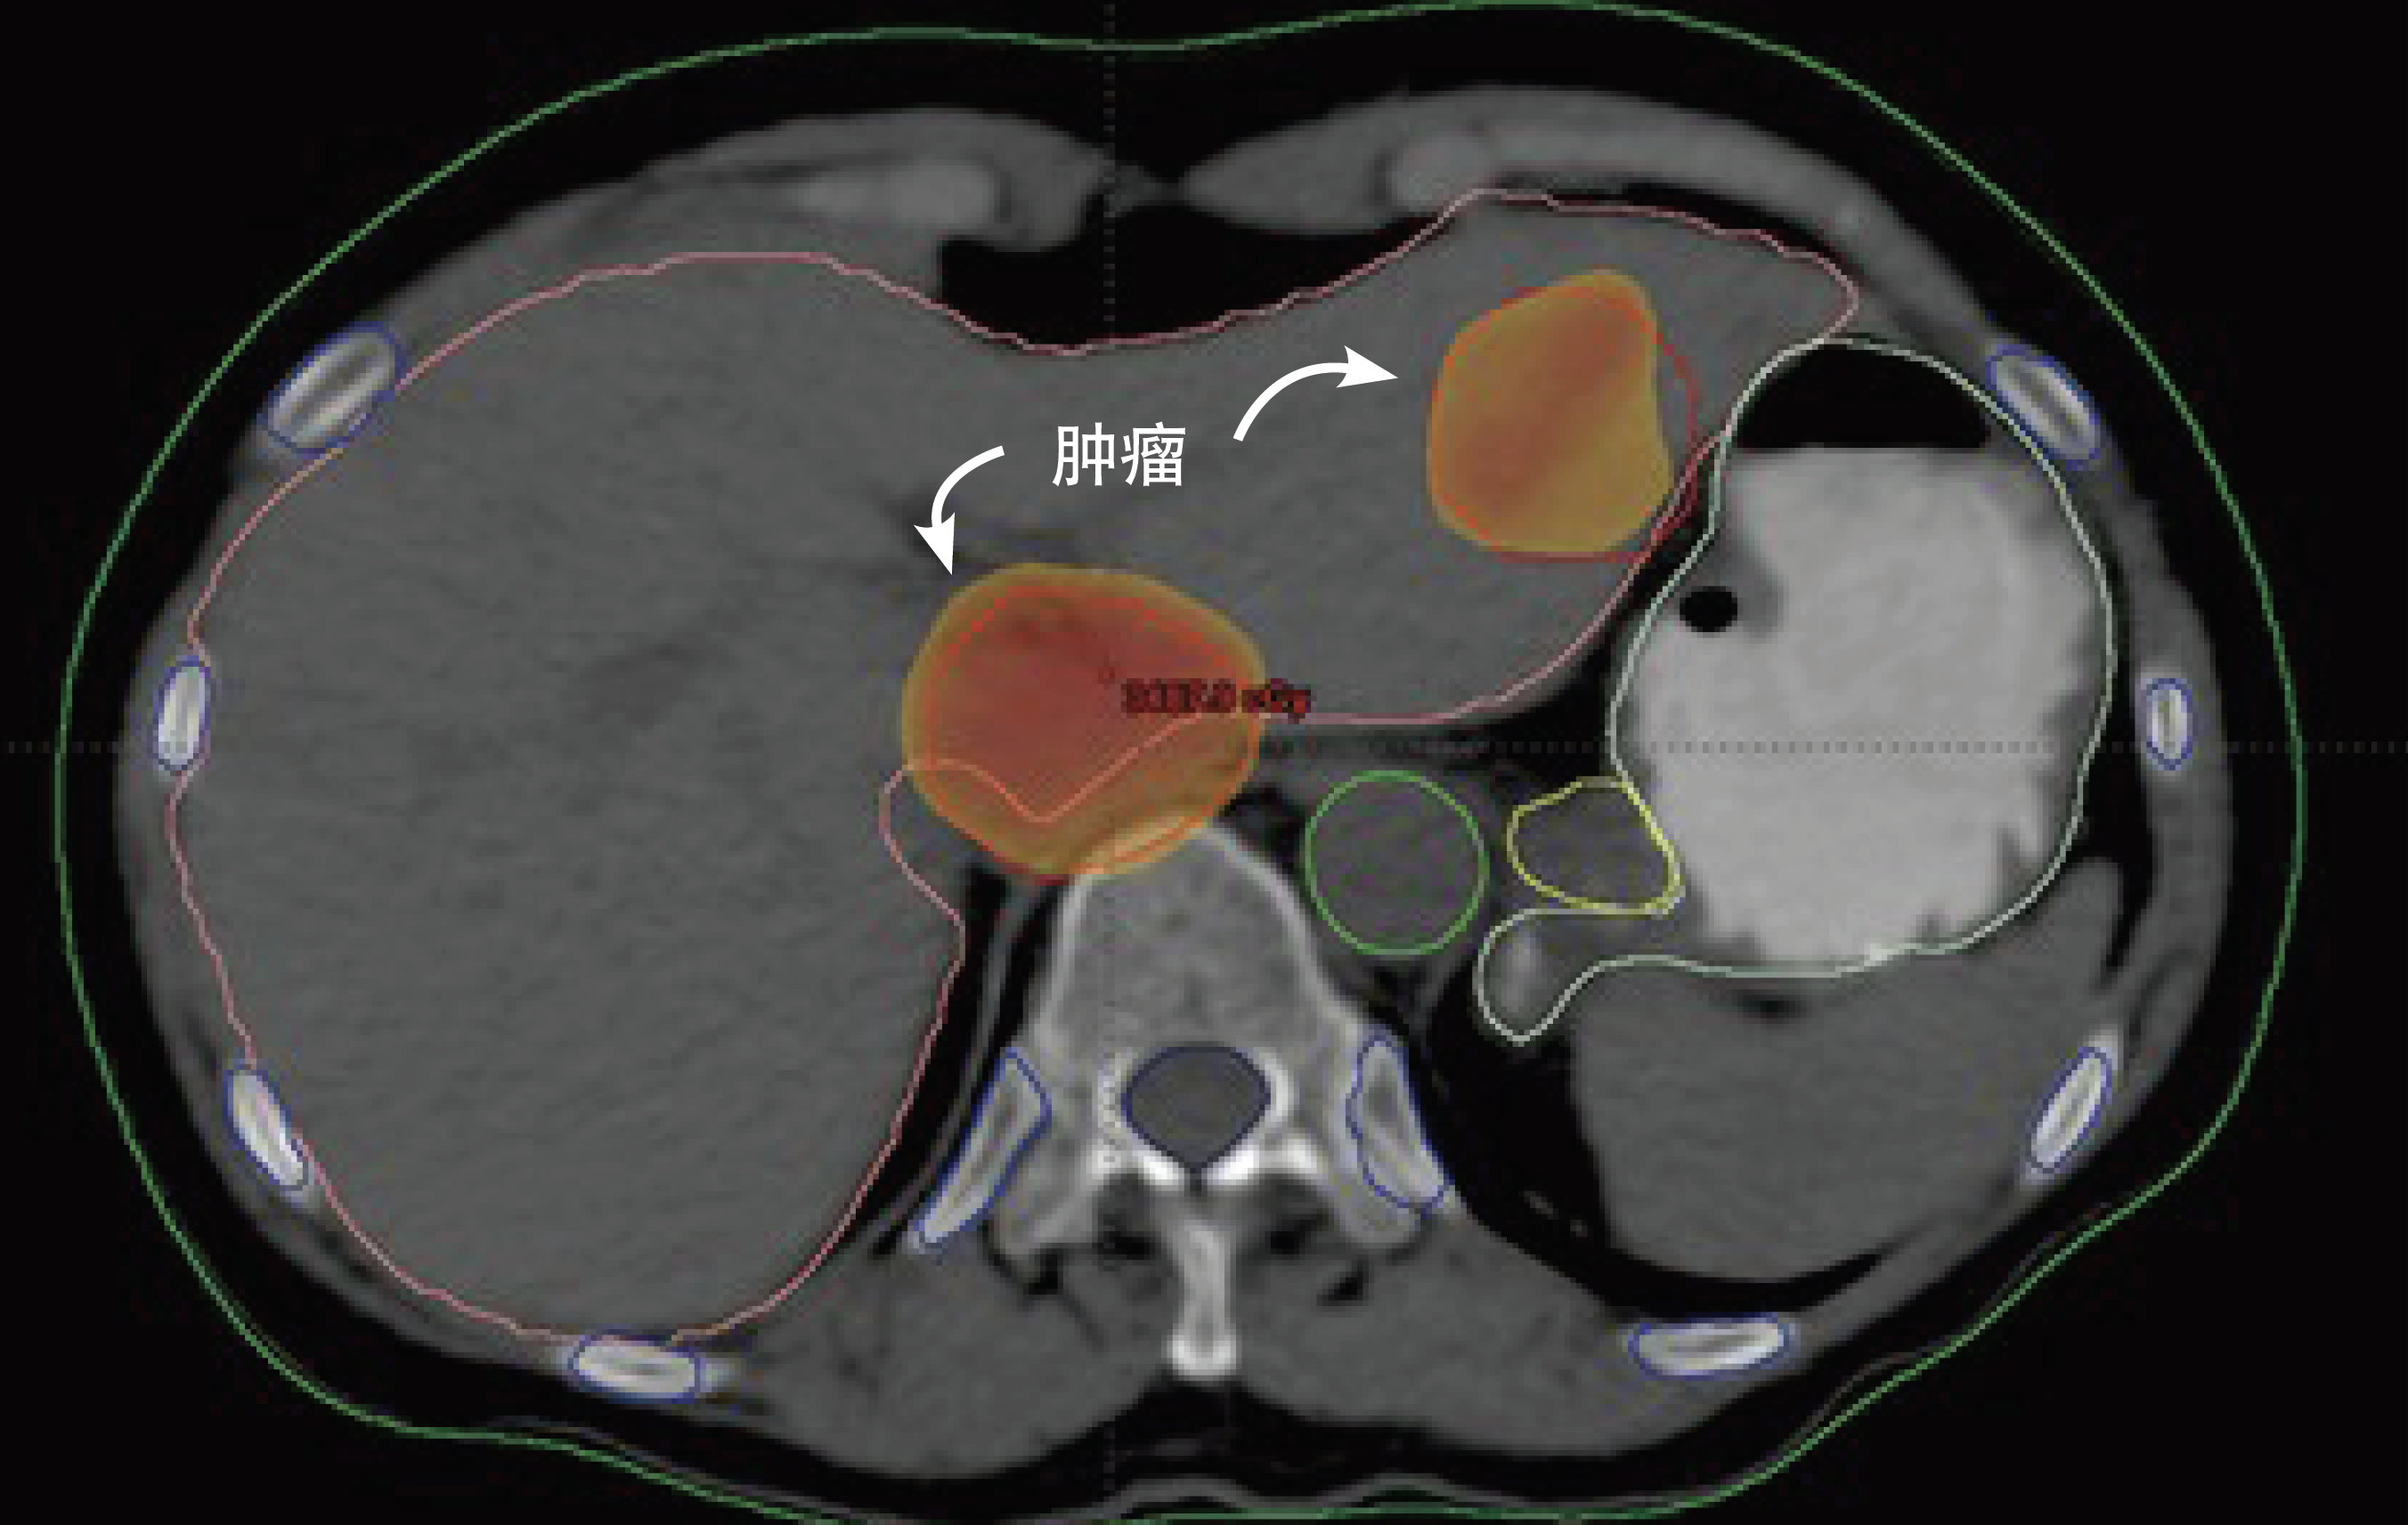

使用一種名為“立體定向體部放療”的先進放療方法治療肝癌的病例。(圖/埃及國家癌癥研究所)

隨著三維近距離放射治療和圖像引導放射治療等工具和程序的出現,這種情況發生了變化。這些治療使用詳細的成像技術來幫助動態引導和調整治療期間的輻射。立體定向體部放療還可以提供高精度的治療,從多個方向施用輻射,并允許在較短的治療時間內大幅提高劑量。

包圍并攻克腫瘤

立體定向體部放療已將控制和精確度提升到另一個層級。它的獨特之處在于使用四維圖像——高度、寬度、深度以及在某些部位移動,從不同角度規劃并對腫瘤施用非常精確的輻射束。每個束線本身具有較低的輻射劑量,這更安全并且降低了對其路徑中正常組織的副作用的風險。當束線會聚在腫瘤處時,它們使癌細胞受到更大的輻射組合劑量。這通常意味著有效治療患者所需的時間變少。

Shouman及埃及國家癌癥研究所團隊,部分通過原子能機構的支持,現正在使用立體定向體部放療治療早期肺癌和復發性頭頸癌,以及一種稱為肝細胞癌的肝癌,這種癌最常見于埃及男性。

Shouman解釋說,對于像肝細胞癌這樣的肝癌,立體定向體部放療已經從根本上改善了放射治療方案。肝癌現在是世界上癌癥死亡的第三大常見原因。多年來,這種形式的癌癥無法使用輻射進行有效治療;由于對周圍健康肝臟組織的風險,常規放射療法不能安全地提供足夠高的輻射劑量來治療肝腫瘤。使用立體定向體部放療,甚至非常小的肝臟腫瘤也可以用較高劑量的輻射進行治療,同時保護健康組織。